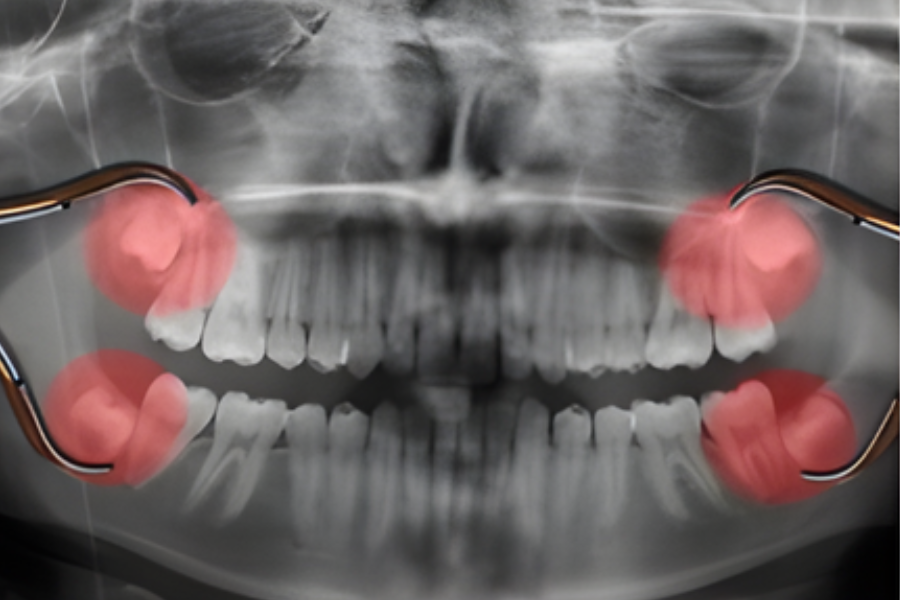

Removal of Wisdom Teeth

Wisdom teeth, also known as third molars, often cause pain, swelling, infections, and misalignment when they do not erupt properly. Our expert oral and maxillofacial surgeon performs safe and precise wisdom tooth extractions, ensuring minimal discomfort and a smooth recovery. Whether your wisdom teeth are impacted, partially erupted, or causing complications, we provide comprehensive evaluation and surgical removal tailored to your needs.

Impaction: When the tooth is trapped under the gums or against another tooth.